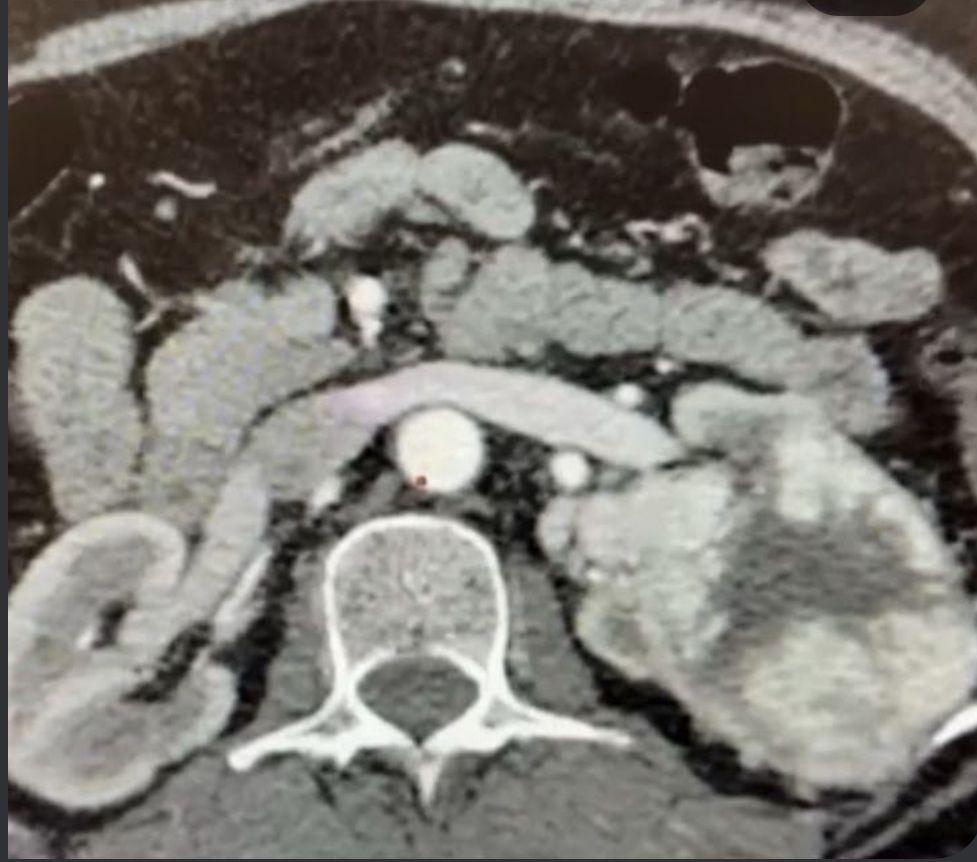

Advancing Urological Oncology: Successful Laparoscopic Nephrectomy

we are committed to offering state-of-the-art care for urological malignancies. Recently, I had the privilege of performing a laparoscopic radical nephrectomy on a 60-year-old lady with a large renal mass.

💡 Highlights of the case:

✅ Minimal blood loss during surgery.

✅ Smooth recovery—patient discharged without complications.

✅ Histopathology revealed clear cell RCC, with negative margins, ensuring she is now cancer-free.